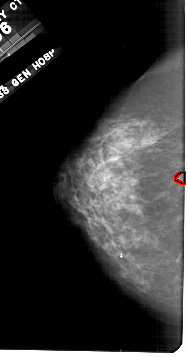

A_1709_1.LEFT_MLO

LEFT_MLO LINES 5491 PIXELS_PER_LINE 2986 BITS_PER_PIXEL 12 RESOLUTION 43.5 OVERLAY

FILE: A_1709_1.LEFT_MLO.OVERLAY

TOTAL_ABNORMALITIES 1

ABNORMALITY 1

LESION_TYPE MASS SHAPE LOBULATED MARGINS CIRCUMSCRIBED

ASSESSMENT 4

SUBTLETY 2

PATHOLOGY BENIGN

TOTAL_OUTLINES 1

BOUNDARY